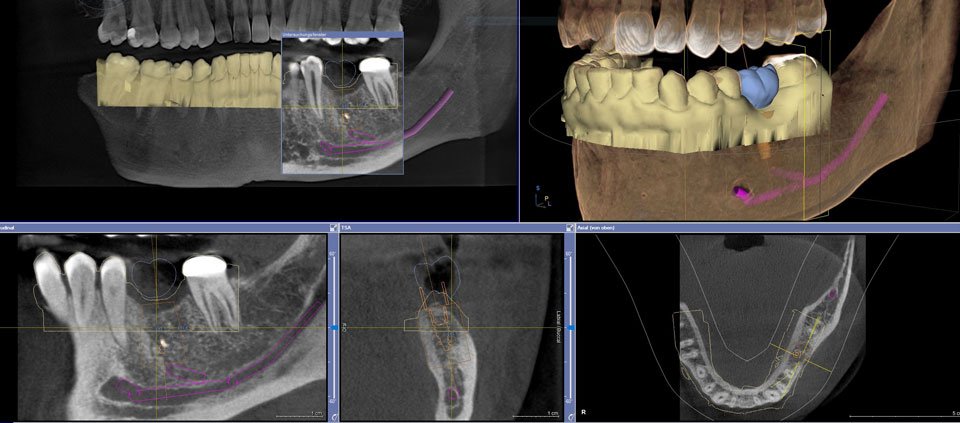

Auf einer herkömmlichen Röntgenaufnahme können Strukturen nur zweidimensional betrachtet werden. Es liegt ein Bild wie eine Art Foto vor.

Der Zahn kann hier nur von einer Seite betrachtet werden. Es besteht nicht die Möglichkeit, „hinter“ den Zahn zu schauen. Bei einer dreidimensionalen Aufnahme kann der Arzt das Bild drehen. Auf diese Weise besteht die Möglichkeit, sich Strukturen von verschiedenen Seiten anzuschauen.

Eine dreidimensionale Röntgenaufnahme bringt immer dann einen Mehrwert, wenn bestimmte Strukturen in ihrer räumlichen Ausdehnung exakt ausgemessen werden sollten. In der Zahnmedizin hilft sie vor allem bei der: